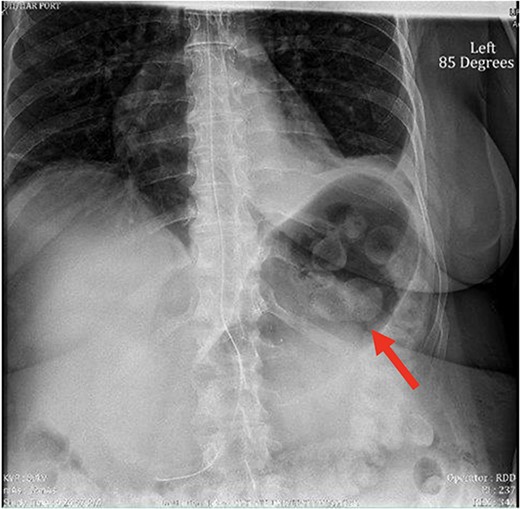

Despite the insertion of the NGT yielding 1500 cc output in 24 hours, the patient continued to experience severe abdominal pain. Urgent abdominal and pelvic computed tomography (CT) scans were taken, as seen in Figs 2–4. The CT scans showed gastric distension and the spleen positioned anteriorly in the right upper quadrant. Consequently, the decision was made to promptly bring the patient to the operating room for a diagnostic laparoscopy with plan to detorse the spleen.

CT of the abdomen and pelvis (coronal slice) showing gastric distention and the spleen positioned in the right upper quadrant.